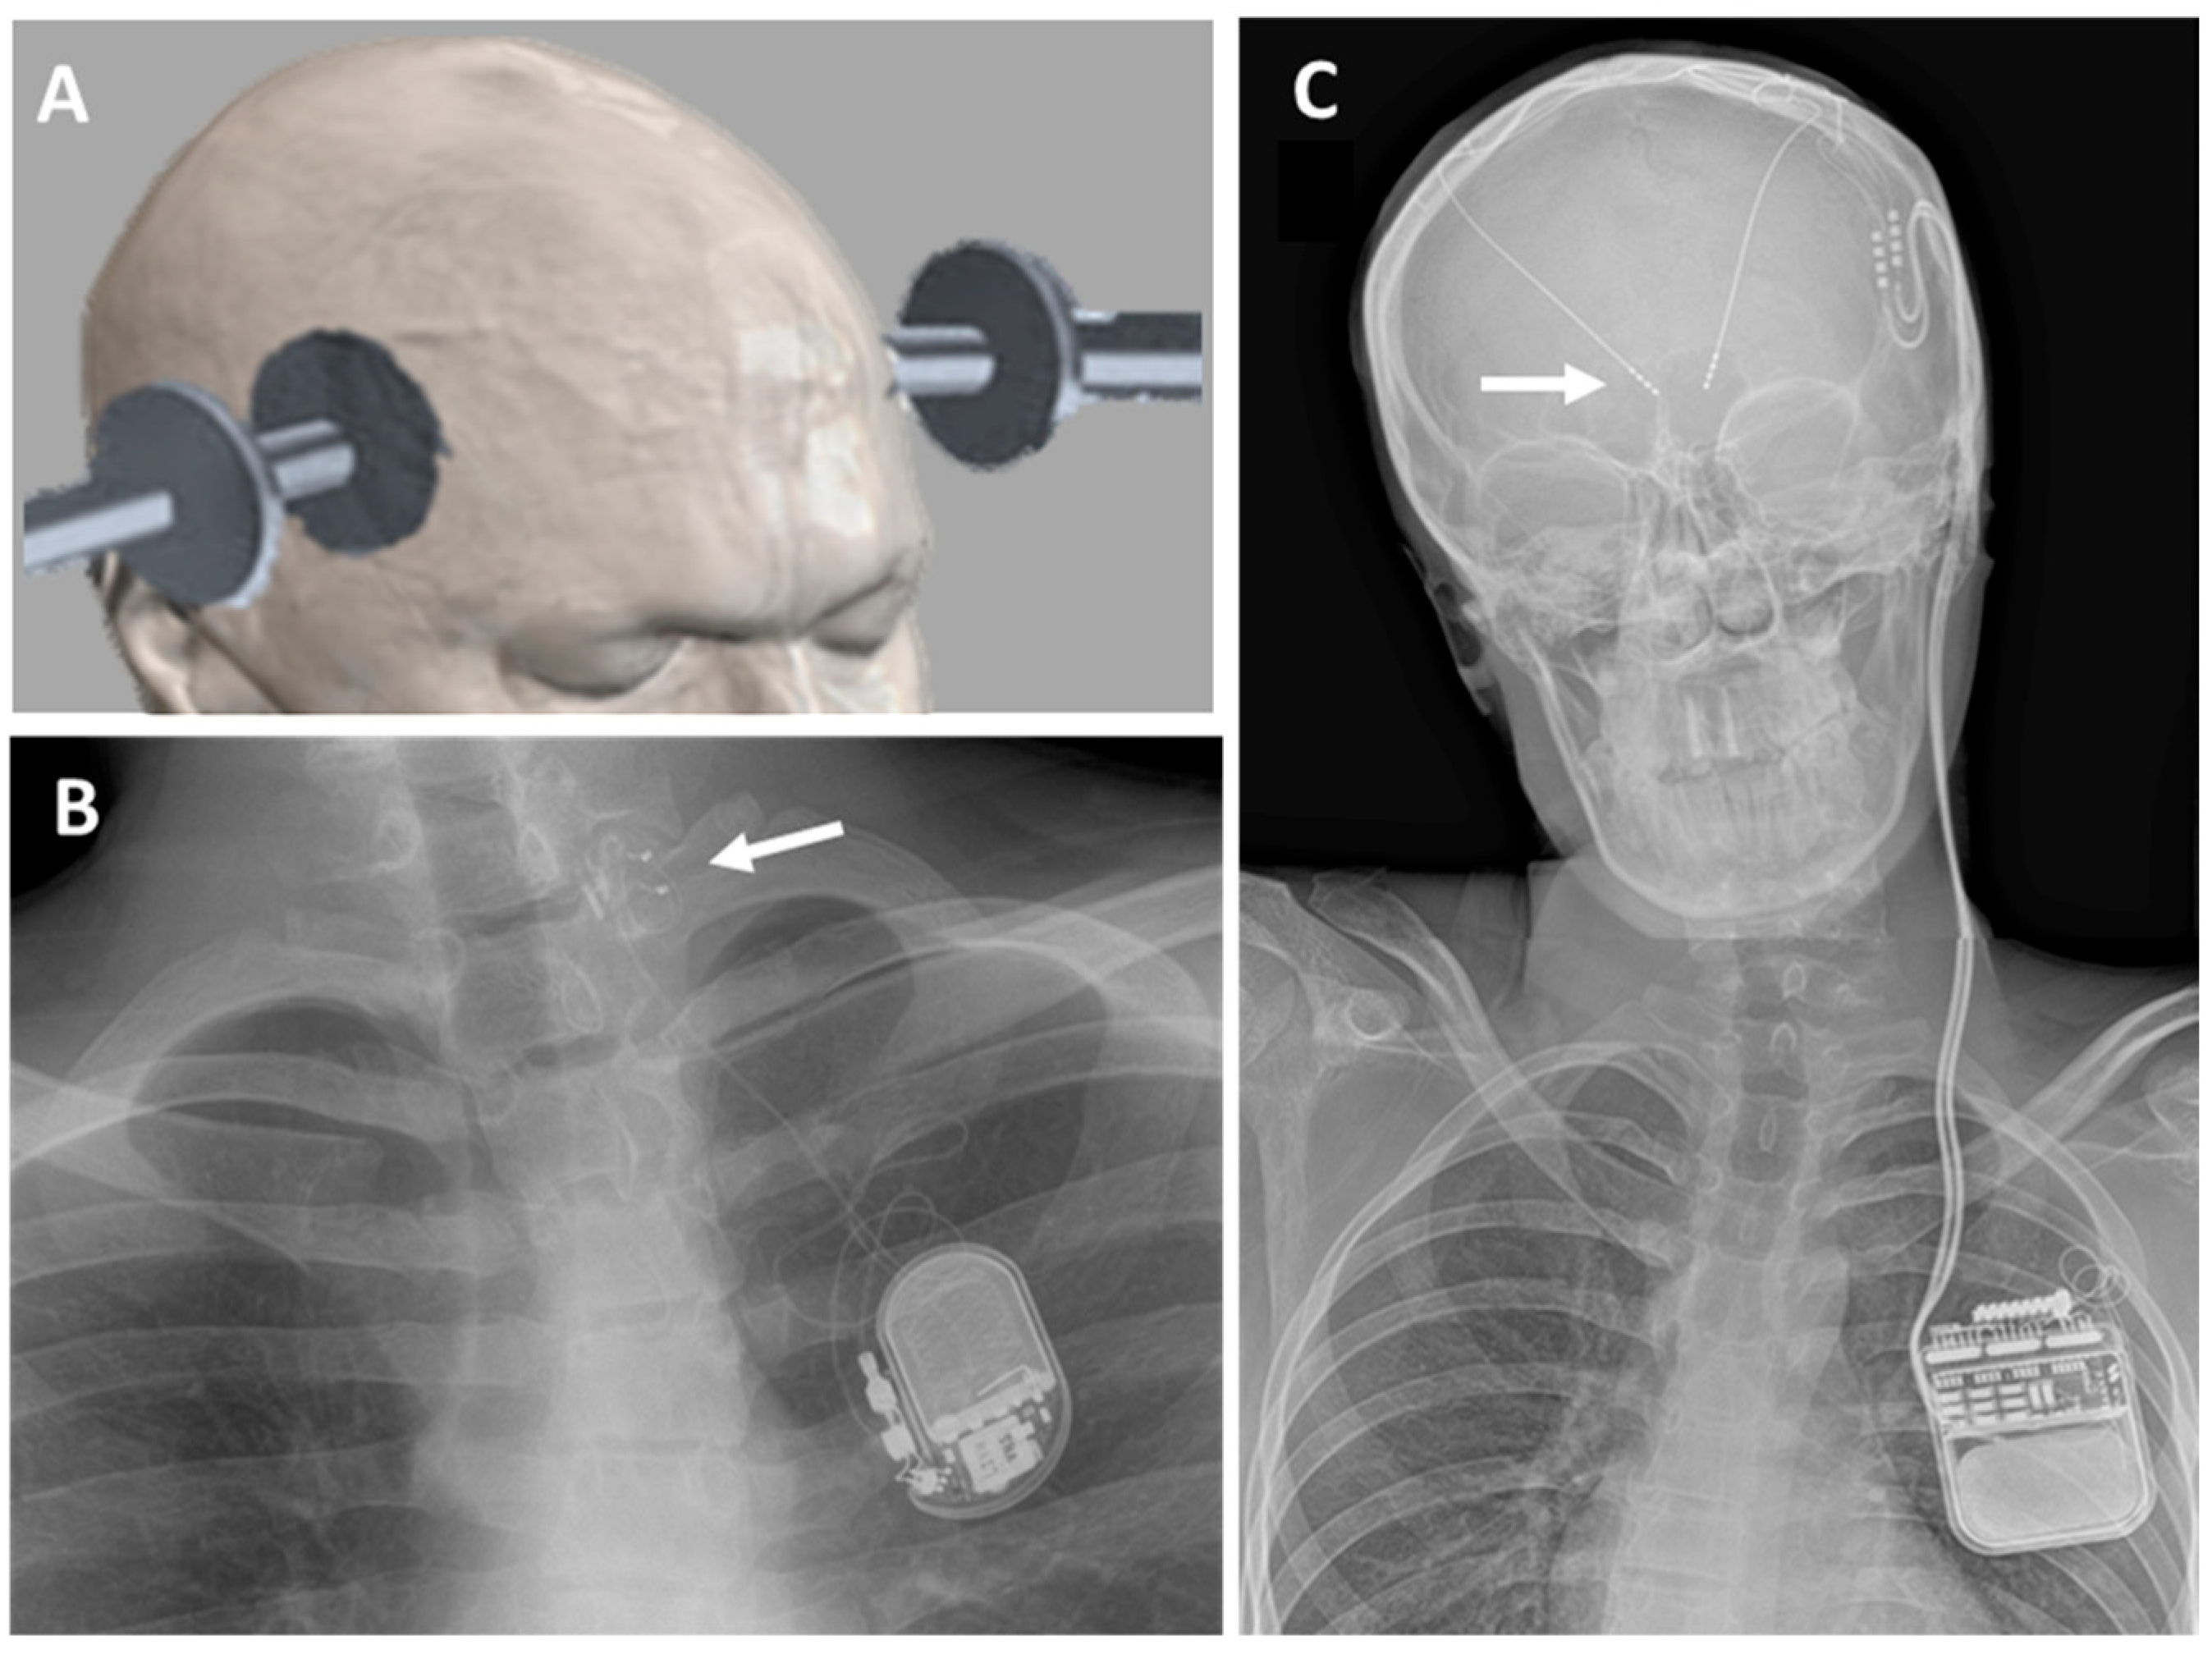

3.2. Vagus Nerve Stimulation (VNS)

3.3. Deep Brain Stimulation (DBS)

4. Discussion